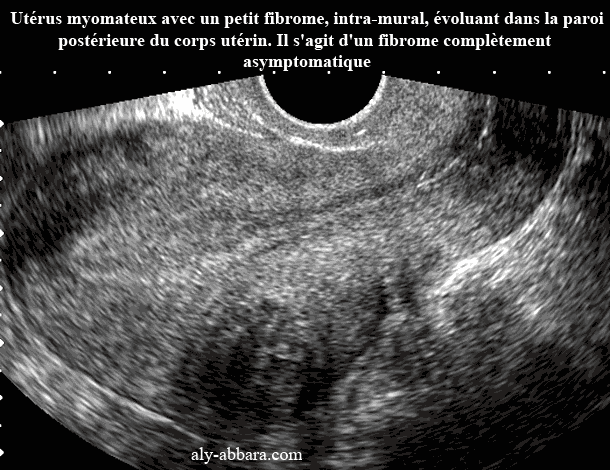

Myome intra-mural asymptomatique

Utérus myomateux avec un petit fibrome, intra-mural, évoluant dans la paroi

postérieure du corps utérin.

Il s'agit d'un fibrome de 26 x 27 mm de diamètre, complètement

asymptomatique.